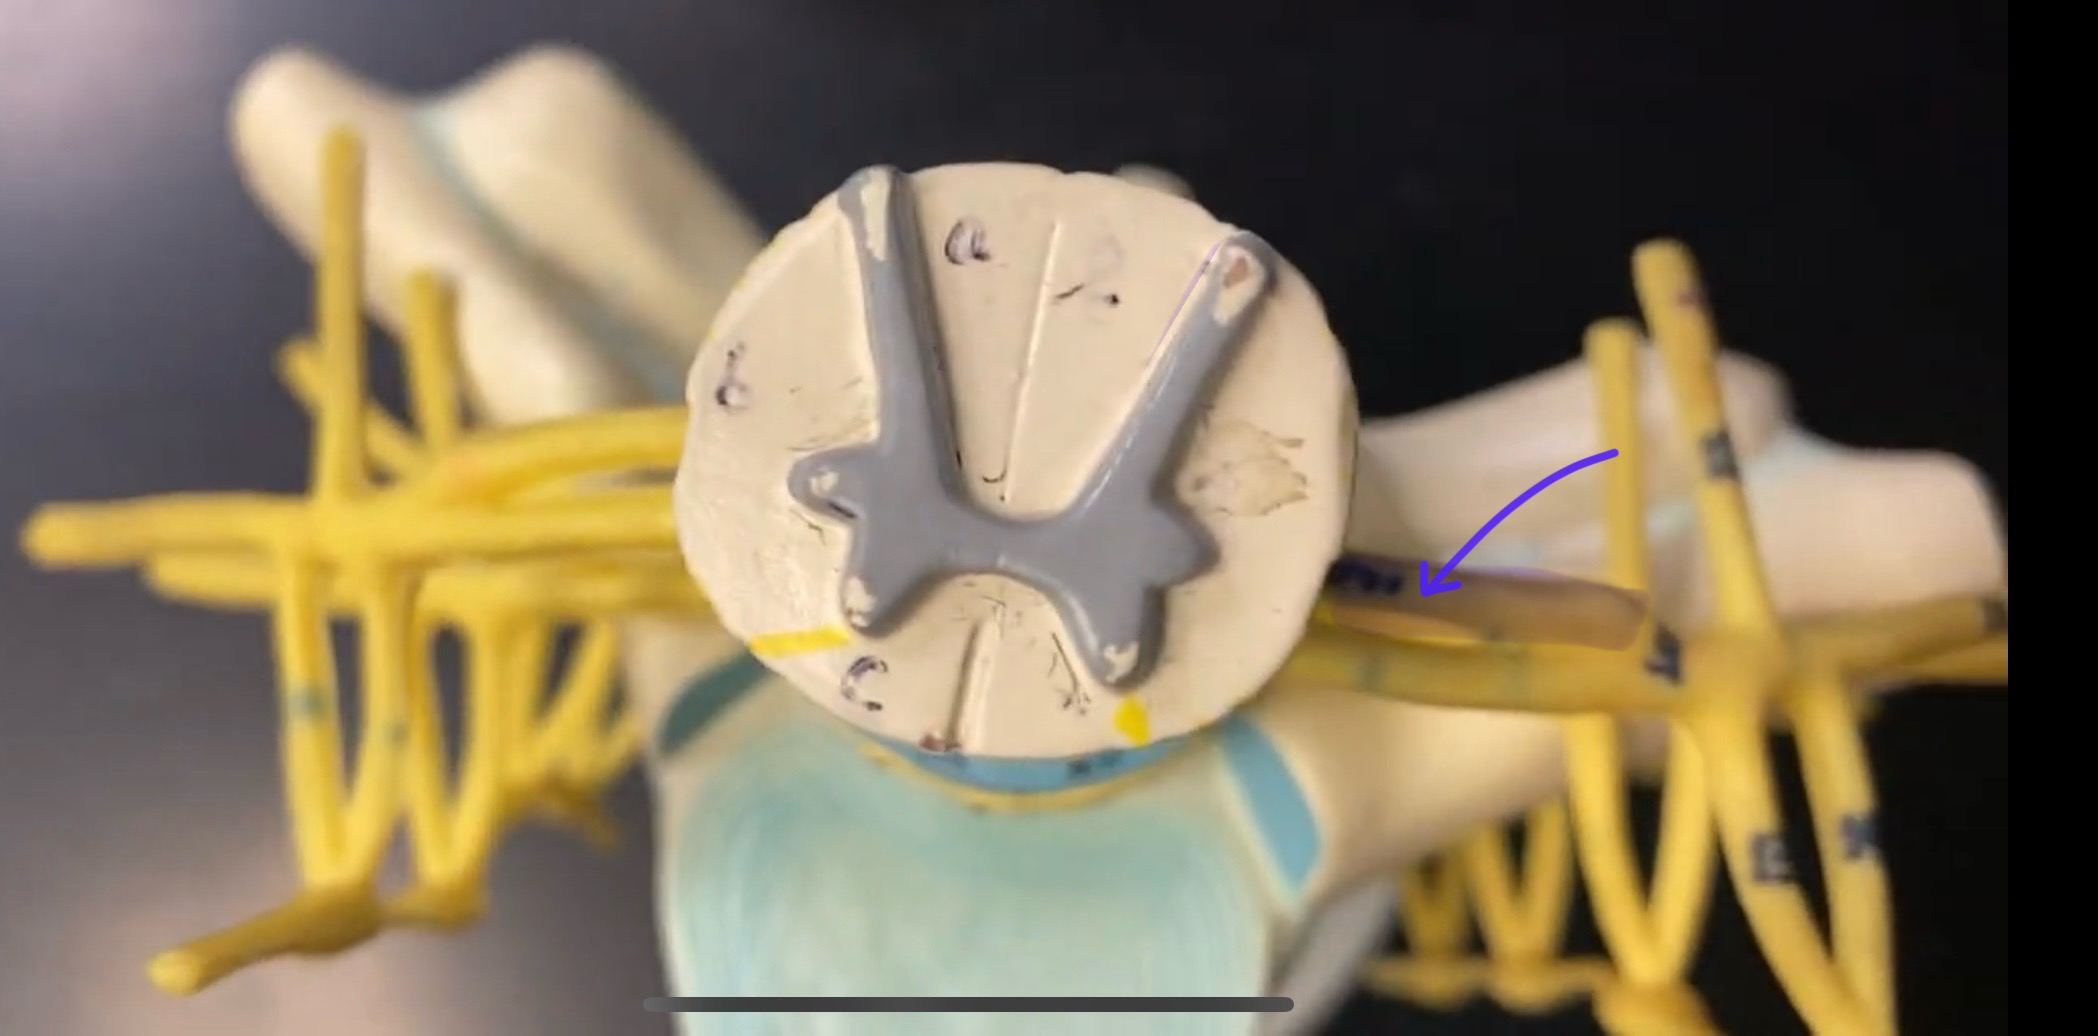

anterior median fissure

posterior median sulcus

posterior (dorsal) horn

anterior (ventral) horn

gray commissure

central canal

anterior column

lateral column

posterior column

white commissure

posterior (dorsal) root

anterior (ventral) root